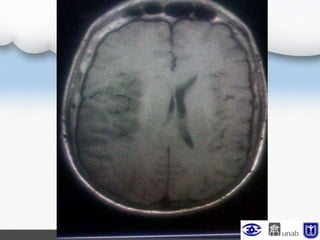

TAC cerebral